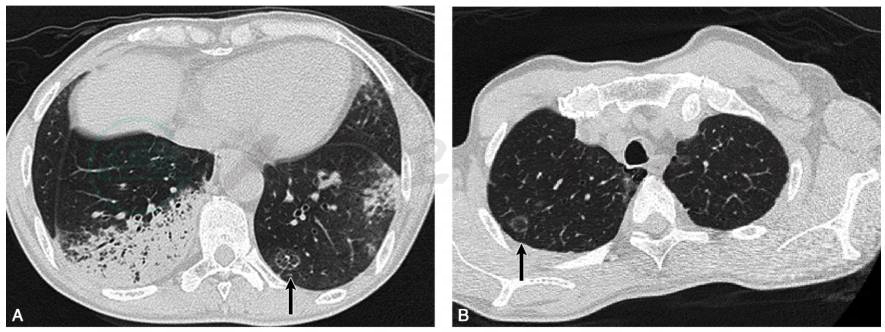

目前患者经验性“哌拉西林/他唑巴坦”联合“左氧氟沙星”足量抗感染治疗已2周,予以复查胸部CT示:两肺多发斑片高密度影,比较前片进展,可见“反晕环征”(图2)。

图2 复查胸部CT表现:两肺多发斑片高密度影,比较前片进展(A),可见“反晕环征”(A、B黑箭所示)